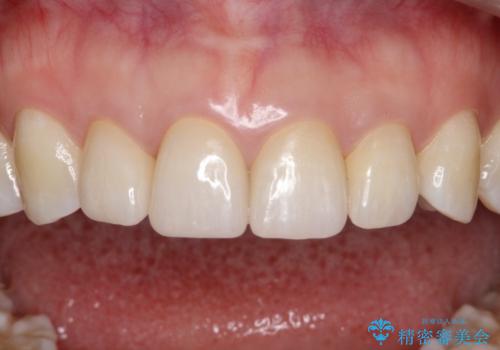

- 天然歯を削ります

- 硬い素材は天然歯を傷つけてしまう場合があります

- かみ合わせや歯ぎしりが強すぎる方はセラミックが割れてしまう可能性があります

- 自費診療(保険適用外治療)となります